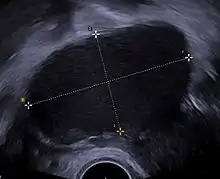

Transvaginal ultrasonography of a hemorrhagic ovarian cyst, probably originating from a corpus luteum cyst. The coagulating blood gives the content a cobweb-like appearance.

Transvaginal ultrasonography of a hemorrhagic ovarian cyst, probably originating from a corpus luteum cyst. The coagulating blood gives the content a cobweb-like appearance.

Ovarian cysts are usually diagnosed by ultrasound, CT scan, or MRI, and correlated with clinical presentation and endocrinologic tests as appropriate.[10]

Ultrasound

Follow-up imaging in women of reproductive age for incidentally discovered simple cysts on ultrasound is not needed until 5 cm, as these are usually normal ovarian follicles. Simple cysts 5 to 7 cm in premenopausal females should be followed yearly. Simple cysts larger than 7 cm require further imaging with MRI or surgical assessment. Because they are large, they cannot be reliably assessed by ultrasound alone; it can be difficult to see posterior wall soft tissue nodularity or thickened septation due to limited ultrasound beam penetrance at this size and depth. For the corpus luteum, a dominant ovulating follicle that typically appears as a cyst with circumferentially thickened walls and crenulated inner margins, follow up is not needed if the cyst is less than 3 cm in diameter. In postmenopausal patients, any simple cyst greater than 1 cm but less than 7 cm needs yearly follow-up, while those greater than 7 cm need MRI or surgical evaluation, similar to reproductive age females.[11]

For multiloculate cysts with thin septation less than 3 mm, surgical evaluation is recommended. The presence of multiloculation suggests a neoplasm, although the thin septation implies that the neoplasm is benign. For any thickened septation, nodularity, vascular flow on color doppler, or growth over several ultrasounds, surgical removal may be considered due to concern of cancer.[11]